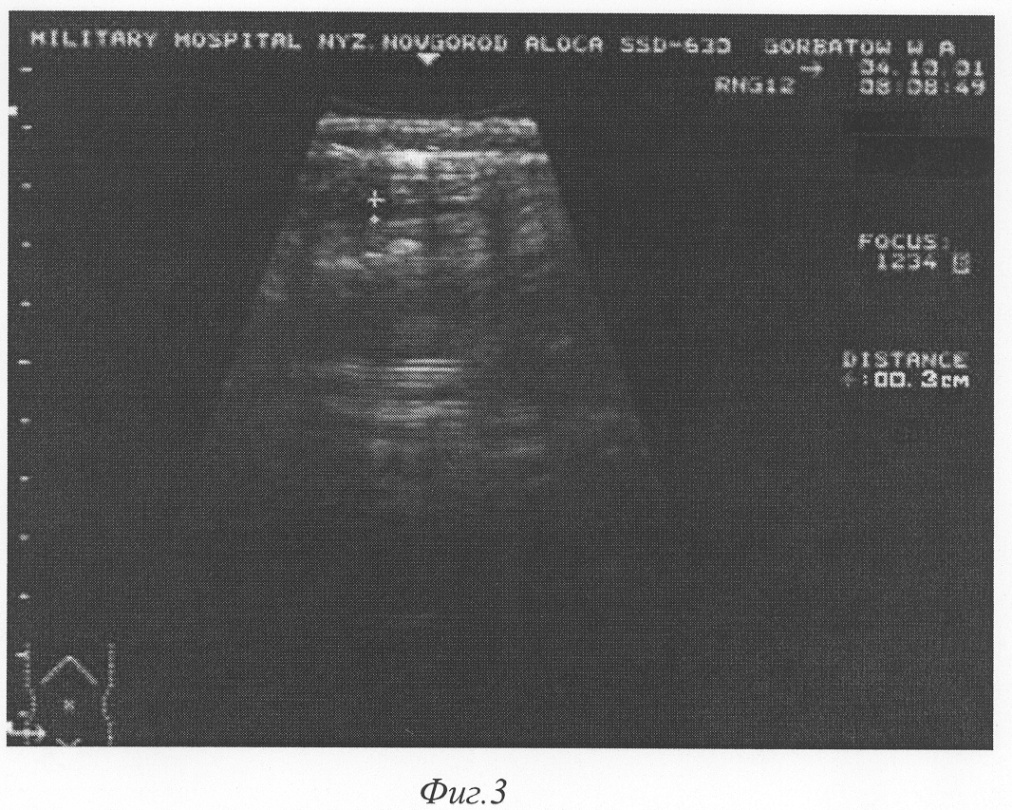

Фиг.3 – эхограмма передней брюшной стенки живота на 3-й день после аппендэктомии больного Д., 19 лет. Определяется гипоэхогенная зона (обозначена крестами) на глубине апоневроза наружной косой мышцы живота толщиной 3 мм.

Пример 2. Больной Д. 19 лет, история болезни №2166, поступил в клинику 06.04.2001 года с диагнозом «Острый аппендицит». Диагноз подтвержден данными анамнеза, объективного обследования и лабораторными показателями. Операция – аппендэктомия. Послеоперационный диагноз: катаральный аппендицит. Операционная рана ушита наглухо. В первые сутки начат курс КВЧ-терапии аппаратом «АМФИТ». Боли в области раны купировались через сутки. Гиперемия в области швов исчезла на 2-е сутки. Средняя температура тела в первые 4 суток послеоперационного периода 36,8°С. При сканировании области послеоперационной раны на 3-и сутки (10.04.01) на глубине апоневроза гипоэхогенная зона толщиной 3 мм (фиг.3). 12.03.01 г. (5-е сутки после операции) гипоэхогенная зона в той же области уменьшилась до 2 мм, на отдельных участках до 1 мм, множественные участки гиперэхогенной зоны (фиг.4). Швы на коже сняты на 5-й день после операции. Заживление раны первичным натяжением. Выписан в удовлетворительном состоянии на 6-е сутки.